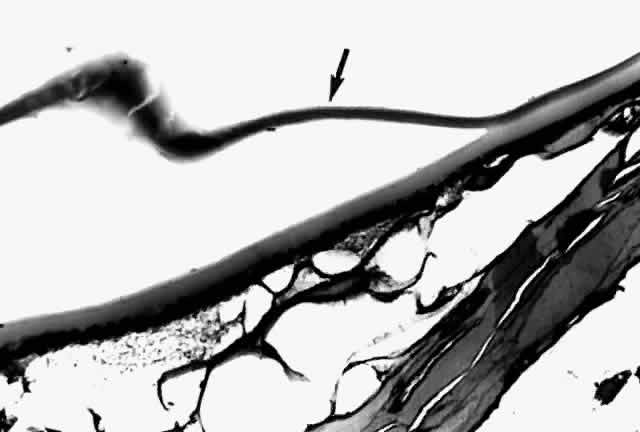

Histologic examination shows an unequal splitting of the anterior capsule (Fig. 1). Electron microscopic examination shows that the lens capsule is laminated and the anterior layer or layers are split free.29 The free portion is quite thin, and it can be rolled or folded over.27

Fig. 1. True exfoliation of the lens capsule. The anterior lens capsule is split and floats away from the rest of the lens (arrow). The subepithelial disruption is artifact. (H & E, magnification × 234; Courtesy of Dr. W.R. Green, Baltimore, MD)

Fig. 9. A. Dark nucleus floating within a liquefied, “milky” cortex settled inferiorly because of gravity. B. Hypermature cataract characterized by a wrinkled anterior capsule (a). No cortex is present (it has liquefied and leaked out); only the nucleus (N) is present. Homogeneity of the nucleus marks it as cataractous. A calcium oxalate crystal (arrow) is present in the nucleus; p' = posterior capsule of lens. A calcium oxalate crystal can be seen within the nucleus before (C) and after (D) polarization. (A, courtesy of Dr. G. Naumann, × 100; D, polarized, H & E × 100)